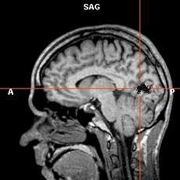

Ученые из Исландии установили генетические причины инсульта

Исследователи из Рейкъявика выявили ген, изменения в котором приводят к развитию наиболее распространенных форм инсульта, сообщает The New York Times.

Как заявляют сотрудники компании Decode Genetics, изменения в новом гене являются не менее значительным фактором риска, чем артериальная гипертензия, повышенный уровень холестерина или курение. Найденный ген ранее никогда не связывался исследователями с инсультом, и его открытие может привести к новым методам профилактики и лечения этого заболевания.

Однако, как отмечают специалисты, говорить о новых подходах в терапии инсульта пока рано: открытие исландских ученых должно быть подверждено в других научных работах. Кроме того, в исследовании принимали участие жители Исландии, что не гарантирует наличия идентичных генетических изменений в других популяциях.

Кроме инсульта, группа исследователей из Рейкъявика под руководством Сольвейг Гретарсдоттир (Solveig Gretarsdottir) работала с другими распространенными заболеваниями, которые принято считать мультифакторными, и обнаружила 12 генов и 20 хромосомных участков, изменения в которых играют большую роль в возникновении этих патологий.